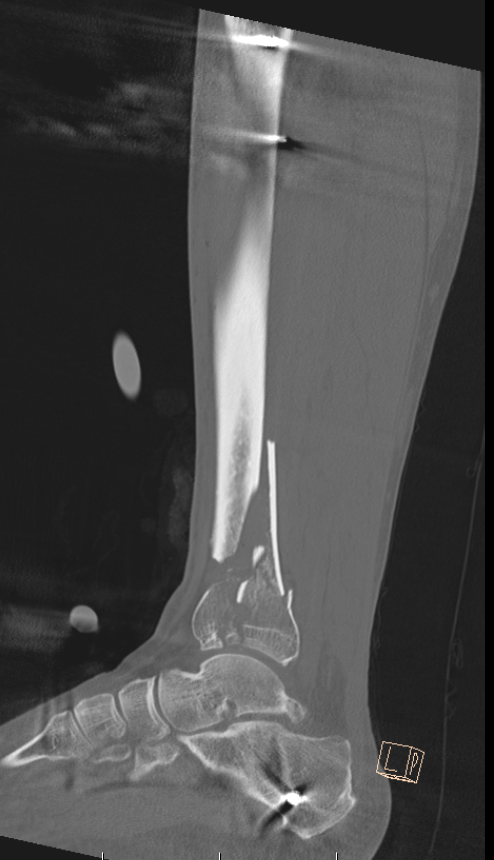

CT after external fixation application

CT scan

Commonly 3 fracture configurations

- medial malleolus

- posterolateral fragment / Volkmann

- anterolateral fragment / Chaput

Tibial plafond common fragmentsTibial plafond fragments